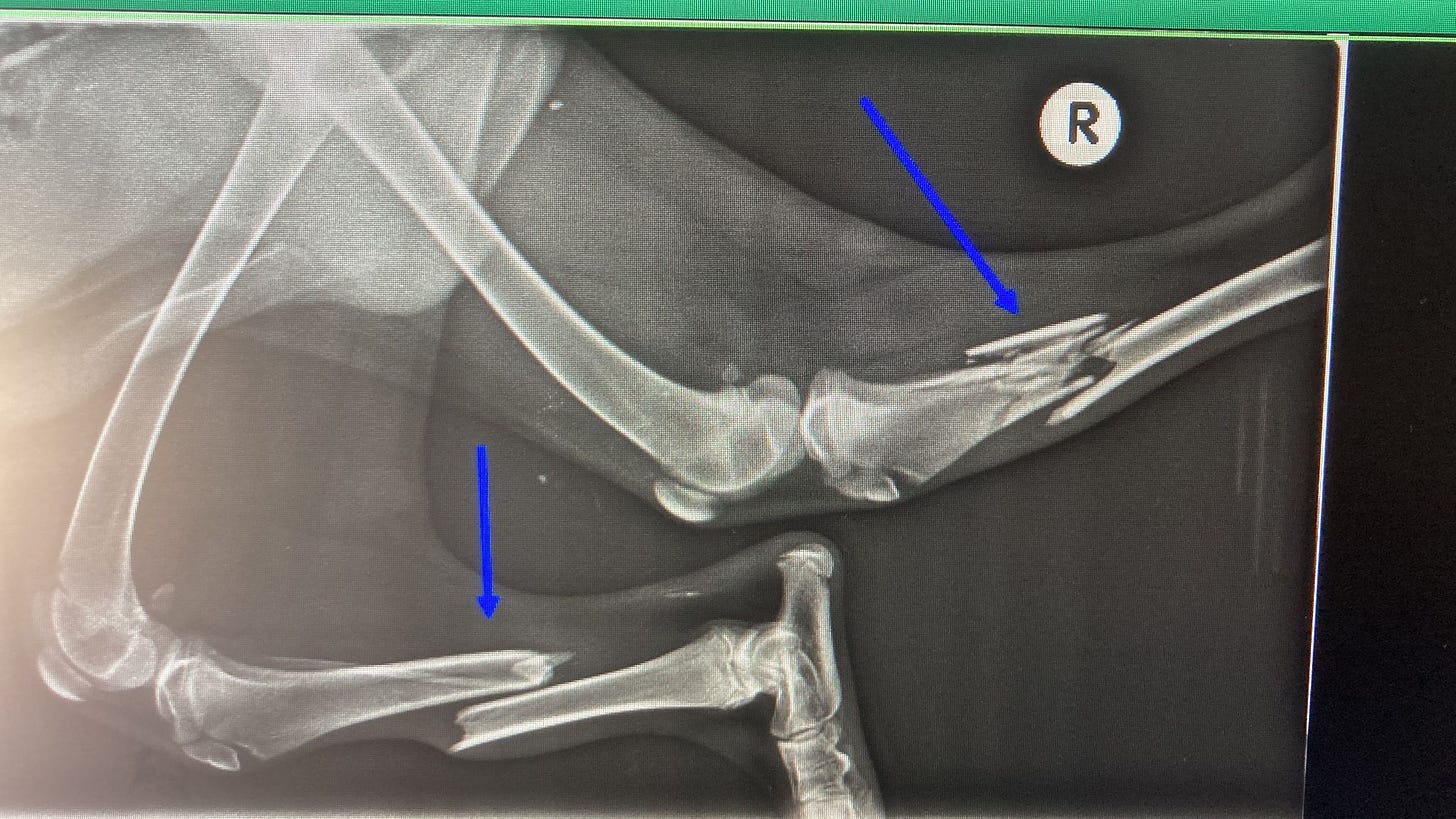

As you can see from the x-rays poor Patch had multiple breaks affecting three of his legs. He must have been in such a great amount of pain & so stressed.

He underwent several surgeries to repair the breaks with the use of plates & he also needed an external fixator.